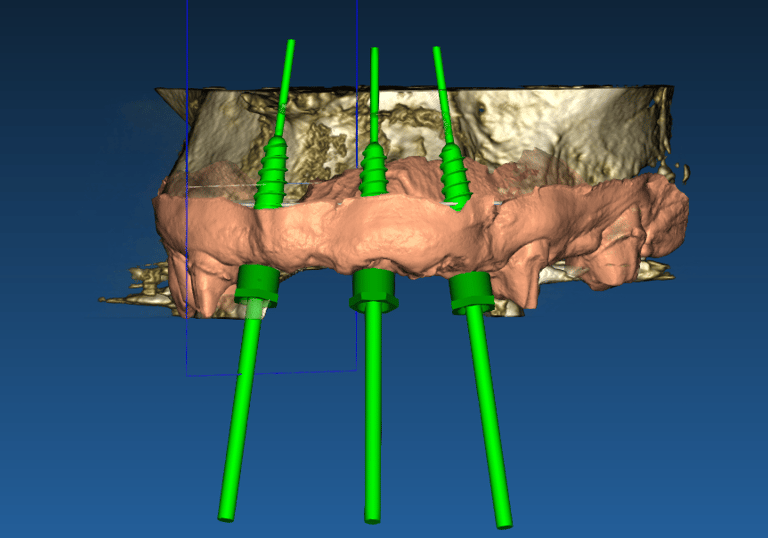

Cirugía guiada por ordenador

Colocar implantes nunca fue tan predecible

Planificación de casos

Situación inicial

Caso donde el paciente demanda estética en maxilar superior. Se retira el puente fijo y nos encontramos con dientes pilares que no pueden ser restaurados. Se indica exodoncia + implantes inmediatos.